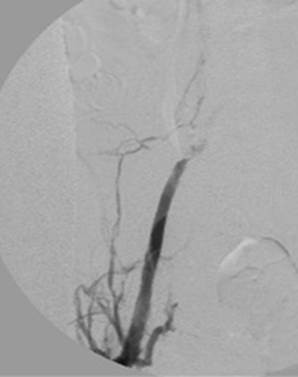

Venograma de la pierna izquierda donde se muestra un trombo oclusivo en las venas profundas más visualizadas.